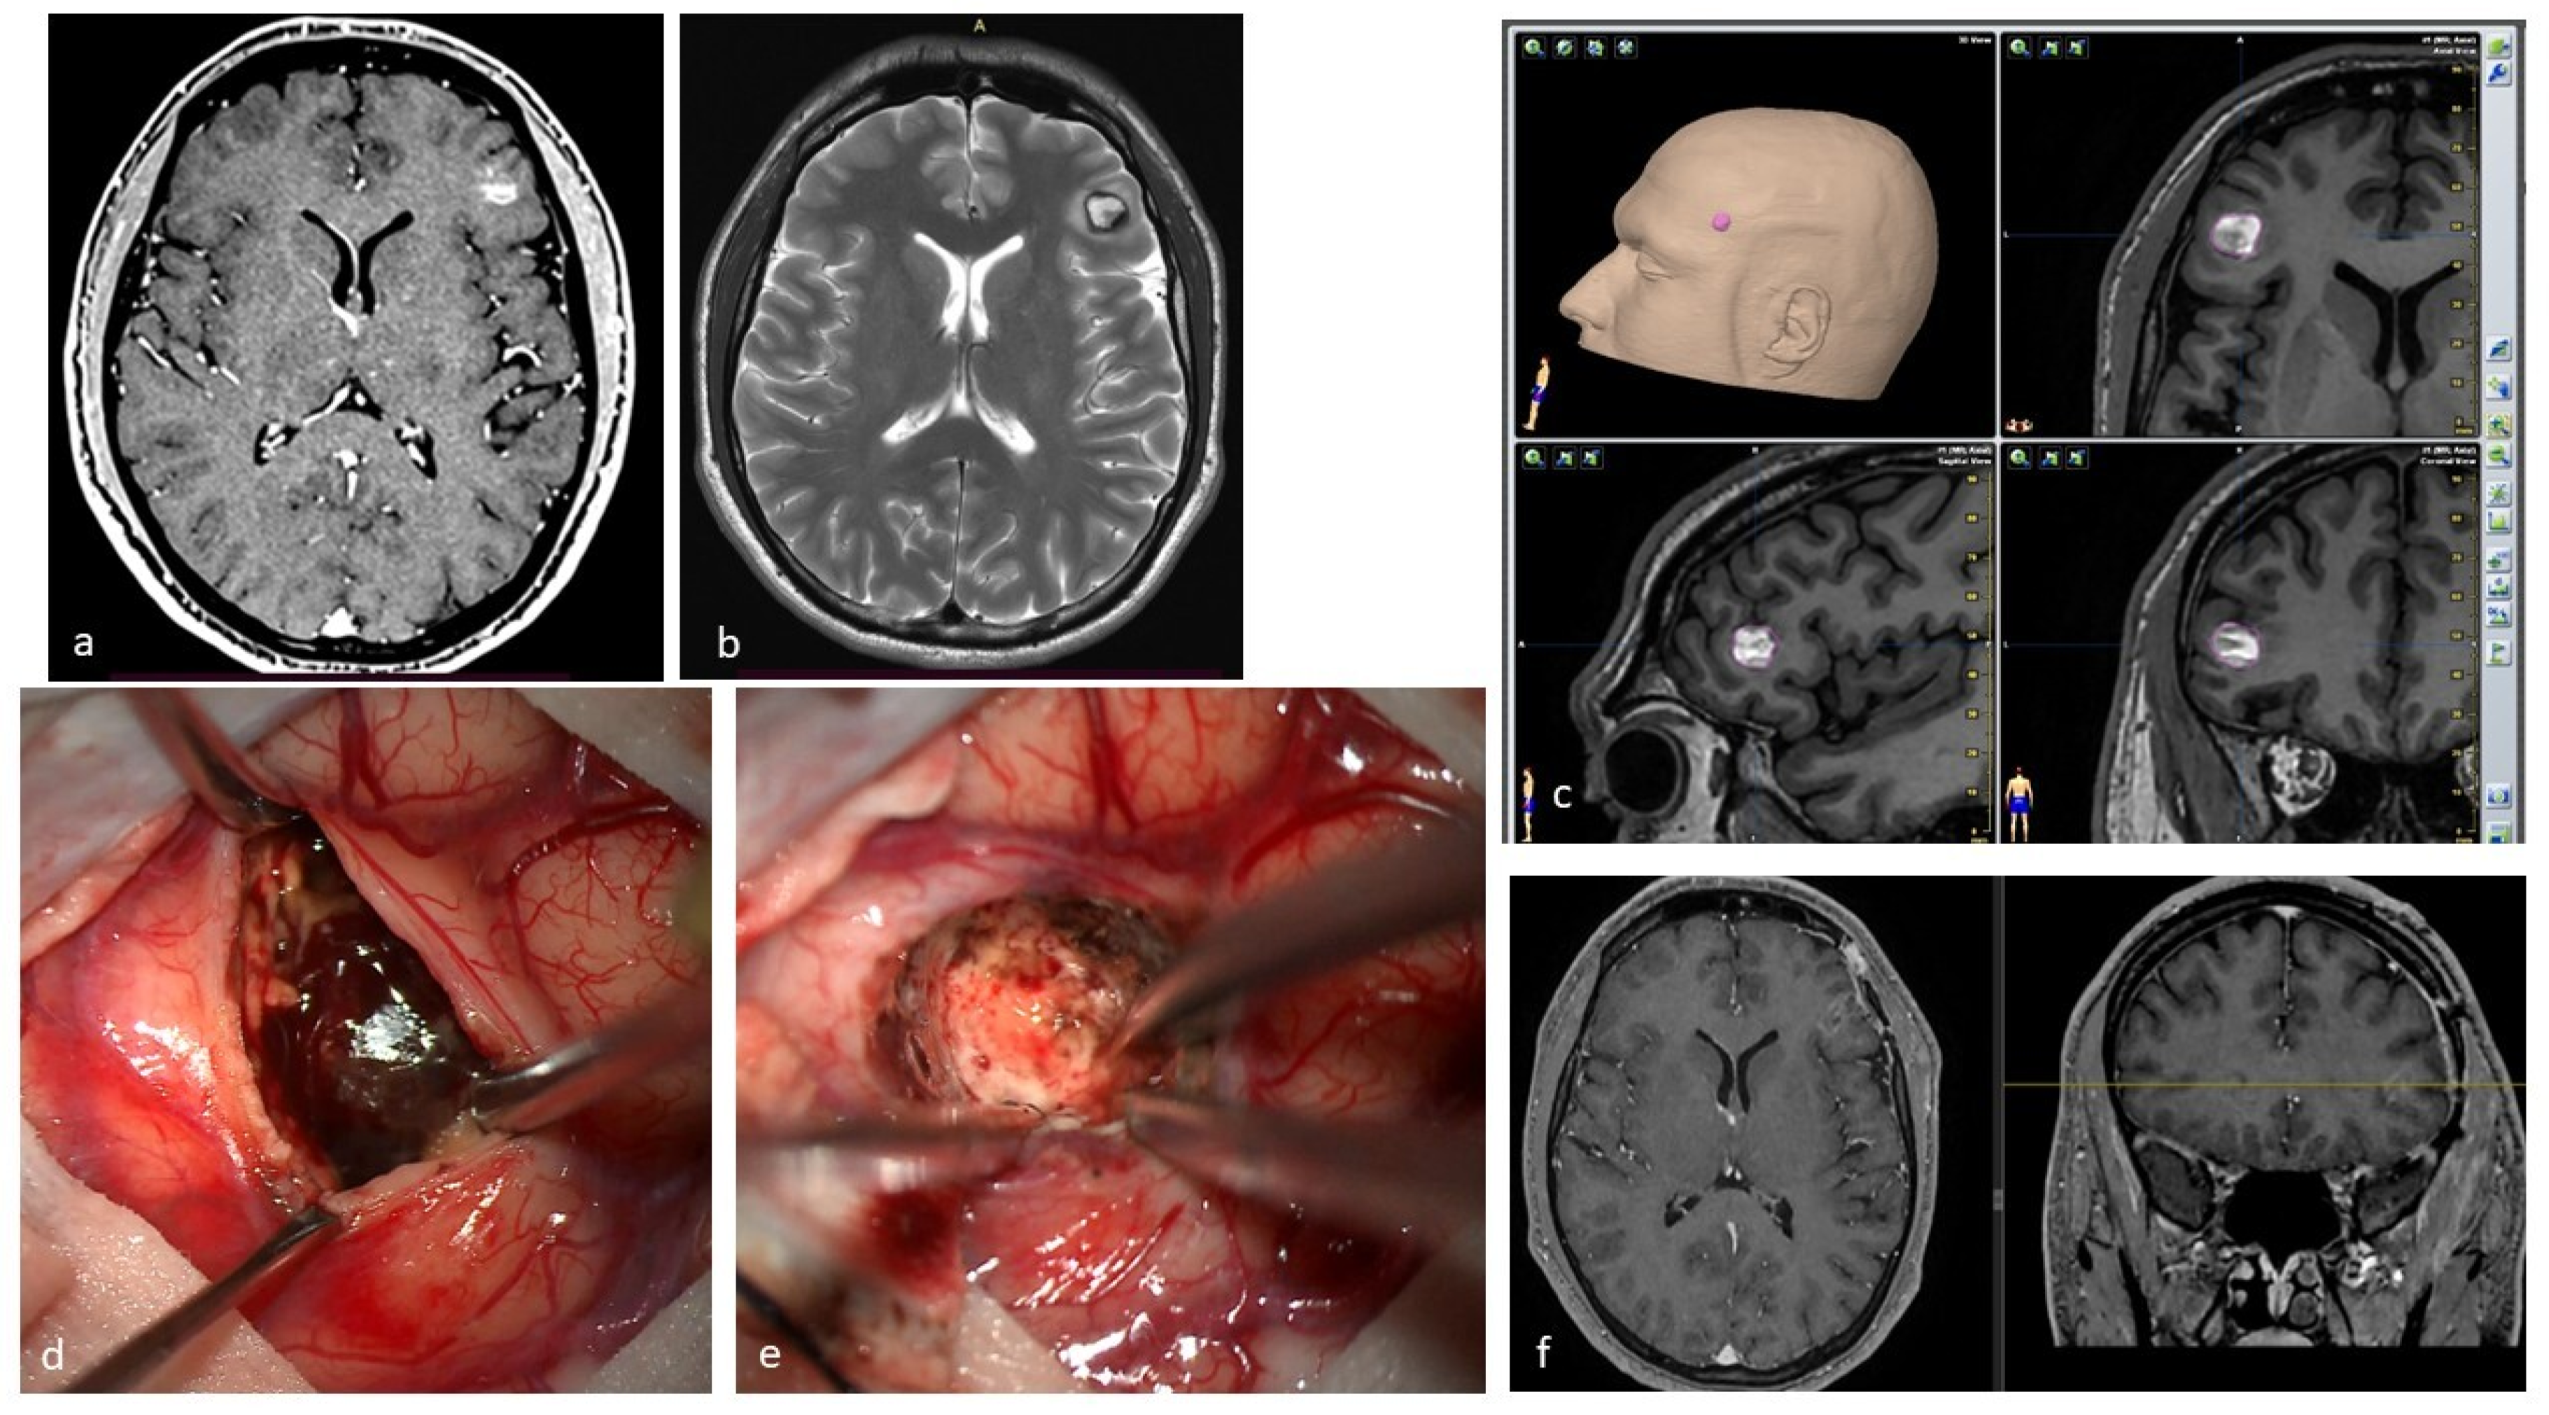

- Daglioglu, E.; Ergungor, F.; Polat, E.; Nacar, O. Microsurgical Resection of Supratentorial Cerebral Cavernomas. Turk. Neurosurg. 2010, 20, 348–352. [Google Scholar] [CrossRef]